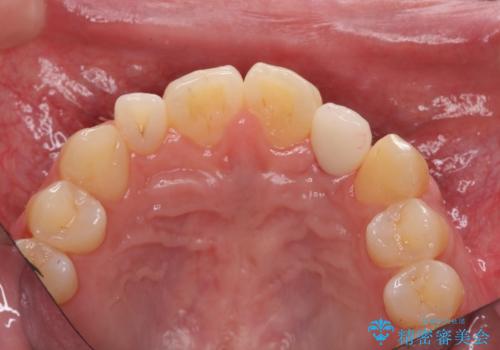

- 前歯の永久歯が元々なく、乳歯を失ったタイミングで前歯の審美性の回復を求めて来院されました。

機能・審美性の回復手段として、インプラント治療・ブリッジ・部分床義歯が考えられます。

それぞれの治療に特徴がありますが、取り外しの必要がなく隣の歯を削る必要も必要ないインプラント治療を選択されました。

前歯部にインプラントを埋入し、きれいに仕上げるためには骨の造成技術や歯肉の厚みを増すような処置を行い、インプラント周囲の環境を整備することが肝要です。